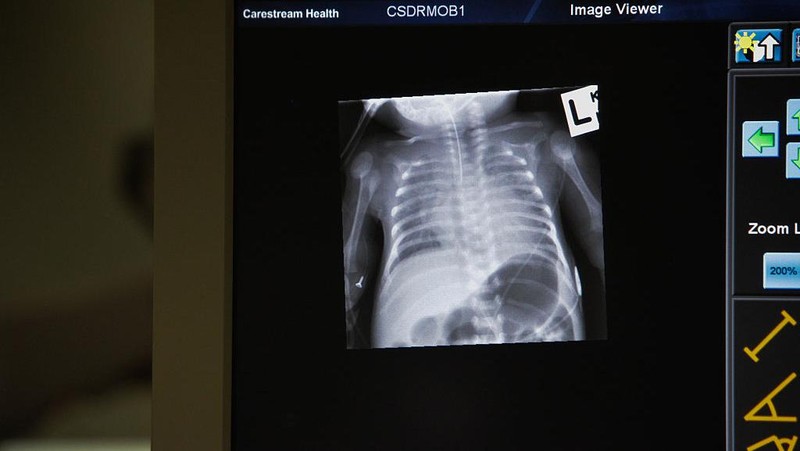

12 Juni 2015 lalu, RS anak di Sydney memperlihatkan sebuah foto rontgen dari dada bayi yang baru lahir prematur.